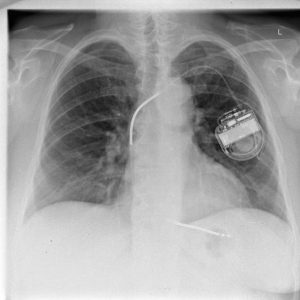

je základní radiologické vyšetření prováděné v ambulantních i lůžkových zařízeních indikované i akutně. Vychází z principu rozdílné absorpce a rozptylu rentgenového záření v jednotlivých tkáních lidského těla ve směru ohnisko – přijímač obrazu. Výsledné zobrazení pak přináší zřetelnou informaci o sledovaných strukturách, kterými jsou skelet, měkké tkáně a struktury s náplní kontrastní látky. Skiagrafický zobrazovací systém umožňuje dosáhnout velkého rozlišení vysokého kontrastu a velkého prostorového rozlišení u zobrazení při možnosti dosažení nízké radiační zátěže pacienta.

Rentgenové vyšetření hrudníku.

Pokud jste nositeli jakéhokoliv elektronického nebo kovového implantátu, případně cizího tělesa, neznamená to automaticky, že nemůžete být vyšetřeni na MR. Takovou skutečnost však musíte VŽDY a PŘED vyšetřením ohlásit obsluze MR zařízení, která kvalifikovaně rozhodne, zda můžete nebo nemůžete vyšetření podstoupit.Využití metody (indikace)

Vyšetření pomocí MR nelze provádět u osob s některými typy elektronických nebo kovových implantátů, případně cizích těles. Nelze především vyšetřovat nemocné s kardiostimulátorem nebo implantovaným defibrilátorem (ICD), poněvadž hrozí vážné poškození jeho funkce, případně závažná až život ohrožující porucha srdečního rytmu. Osoby s kovovými cévními svorkami po operaci mozkových tepenných aneuryzmat (výdutí) lze vyšetřit pomocí MR jen za přísně specifikovaných podmínek.